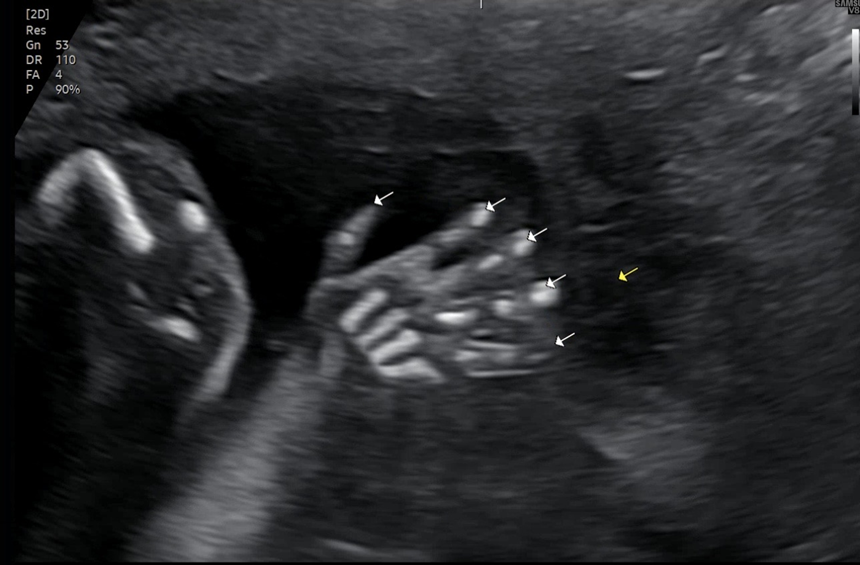

정밀초음파 검사는 약 20분 정도 소요됐어요. 병원 가기 전 아기가 조금 더 활발히 움직일 수 있도록 초코우유를 한 팩 마시고 갔고 덕분에 검사 중 아기가 잘 움직여서 선생님도 주수에 맞게 건강하게 잘 자라고 있다고 하셨어요.

아기의 손가락, 발가락, 척추 선명한 모습까지 모든 걸 자세히 보여주시는데 그 순간은 정말 감동 그 자체였어요.